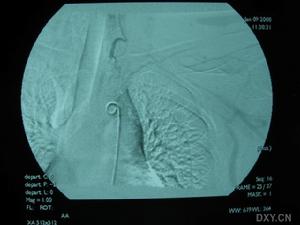

3.腦血管造影有一定的診斷價值71%以上的患者有典型的血管多灶性損害的表現,血管粗細不均,可呈節段性的狹窄或擴張血管阻塞及血管排空延遲等似“臘腸”樣改變,提示腦部血管炎的存在但不能明確是本病的血管炎其他的腦部繼發性血管炎也可有類似的表現有些可因受累的血管太小,腦血管造影可正常

除中樞神經系統症狀外可有發熱、體重下降等全身表現。腦脊液檢查可有細胞數及蛋白的升高,寡克隆區帶陽性。腦活檢可見肉芽腫樣血管炎和/或壞死性血管炎的表現。血管造影可見大腦中小動脈節段性狹窄、擴張及串珠樣改變。1988年Calabrese和Mallek提出了PACNS的診斷標準:①病史和臨床檢查發現原因不明的後天獲得性神經系統損害。②腦血管造影或腦活檢發現有典型血管炎表現。③除外系統性血管炎及其他能引起繼發性中樞神經系統血管炎(血管異常及組織學改變)的各種情況。本例基本皆符合此三條標準。